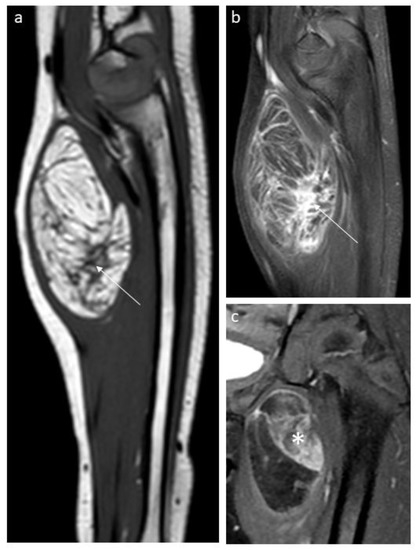

3.1. Lipoblastoma and Lipoma

3.5. Liposarcoma

3.6. Liposarcoma vs. Benign Tumor